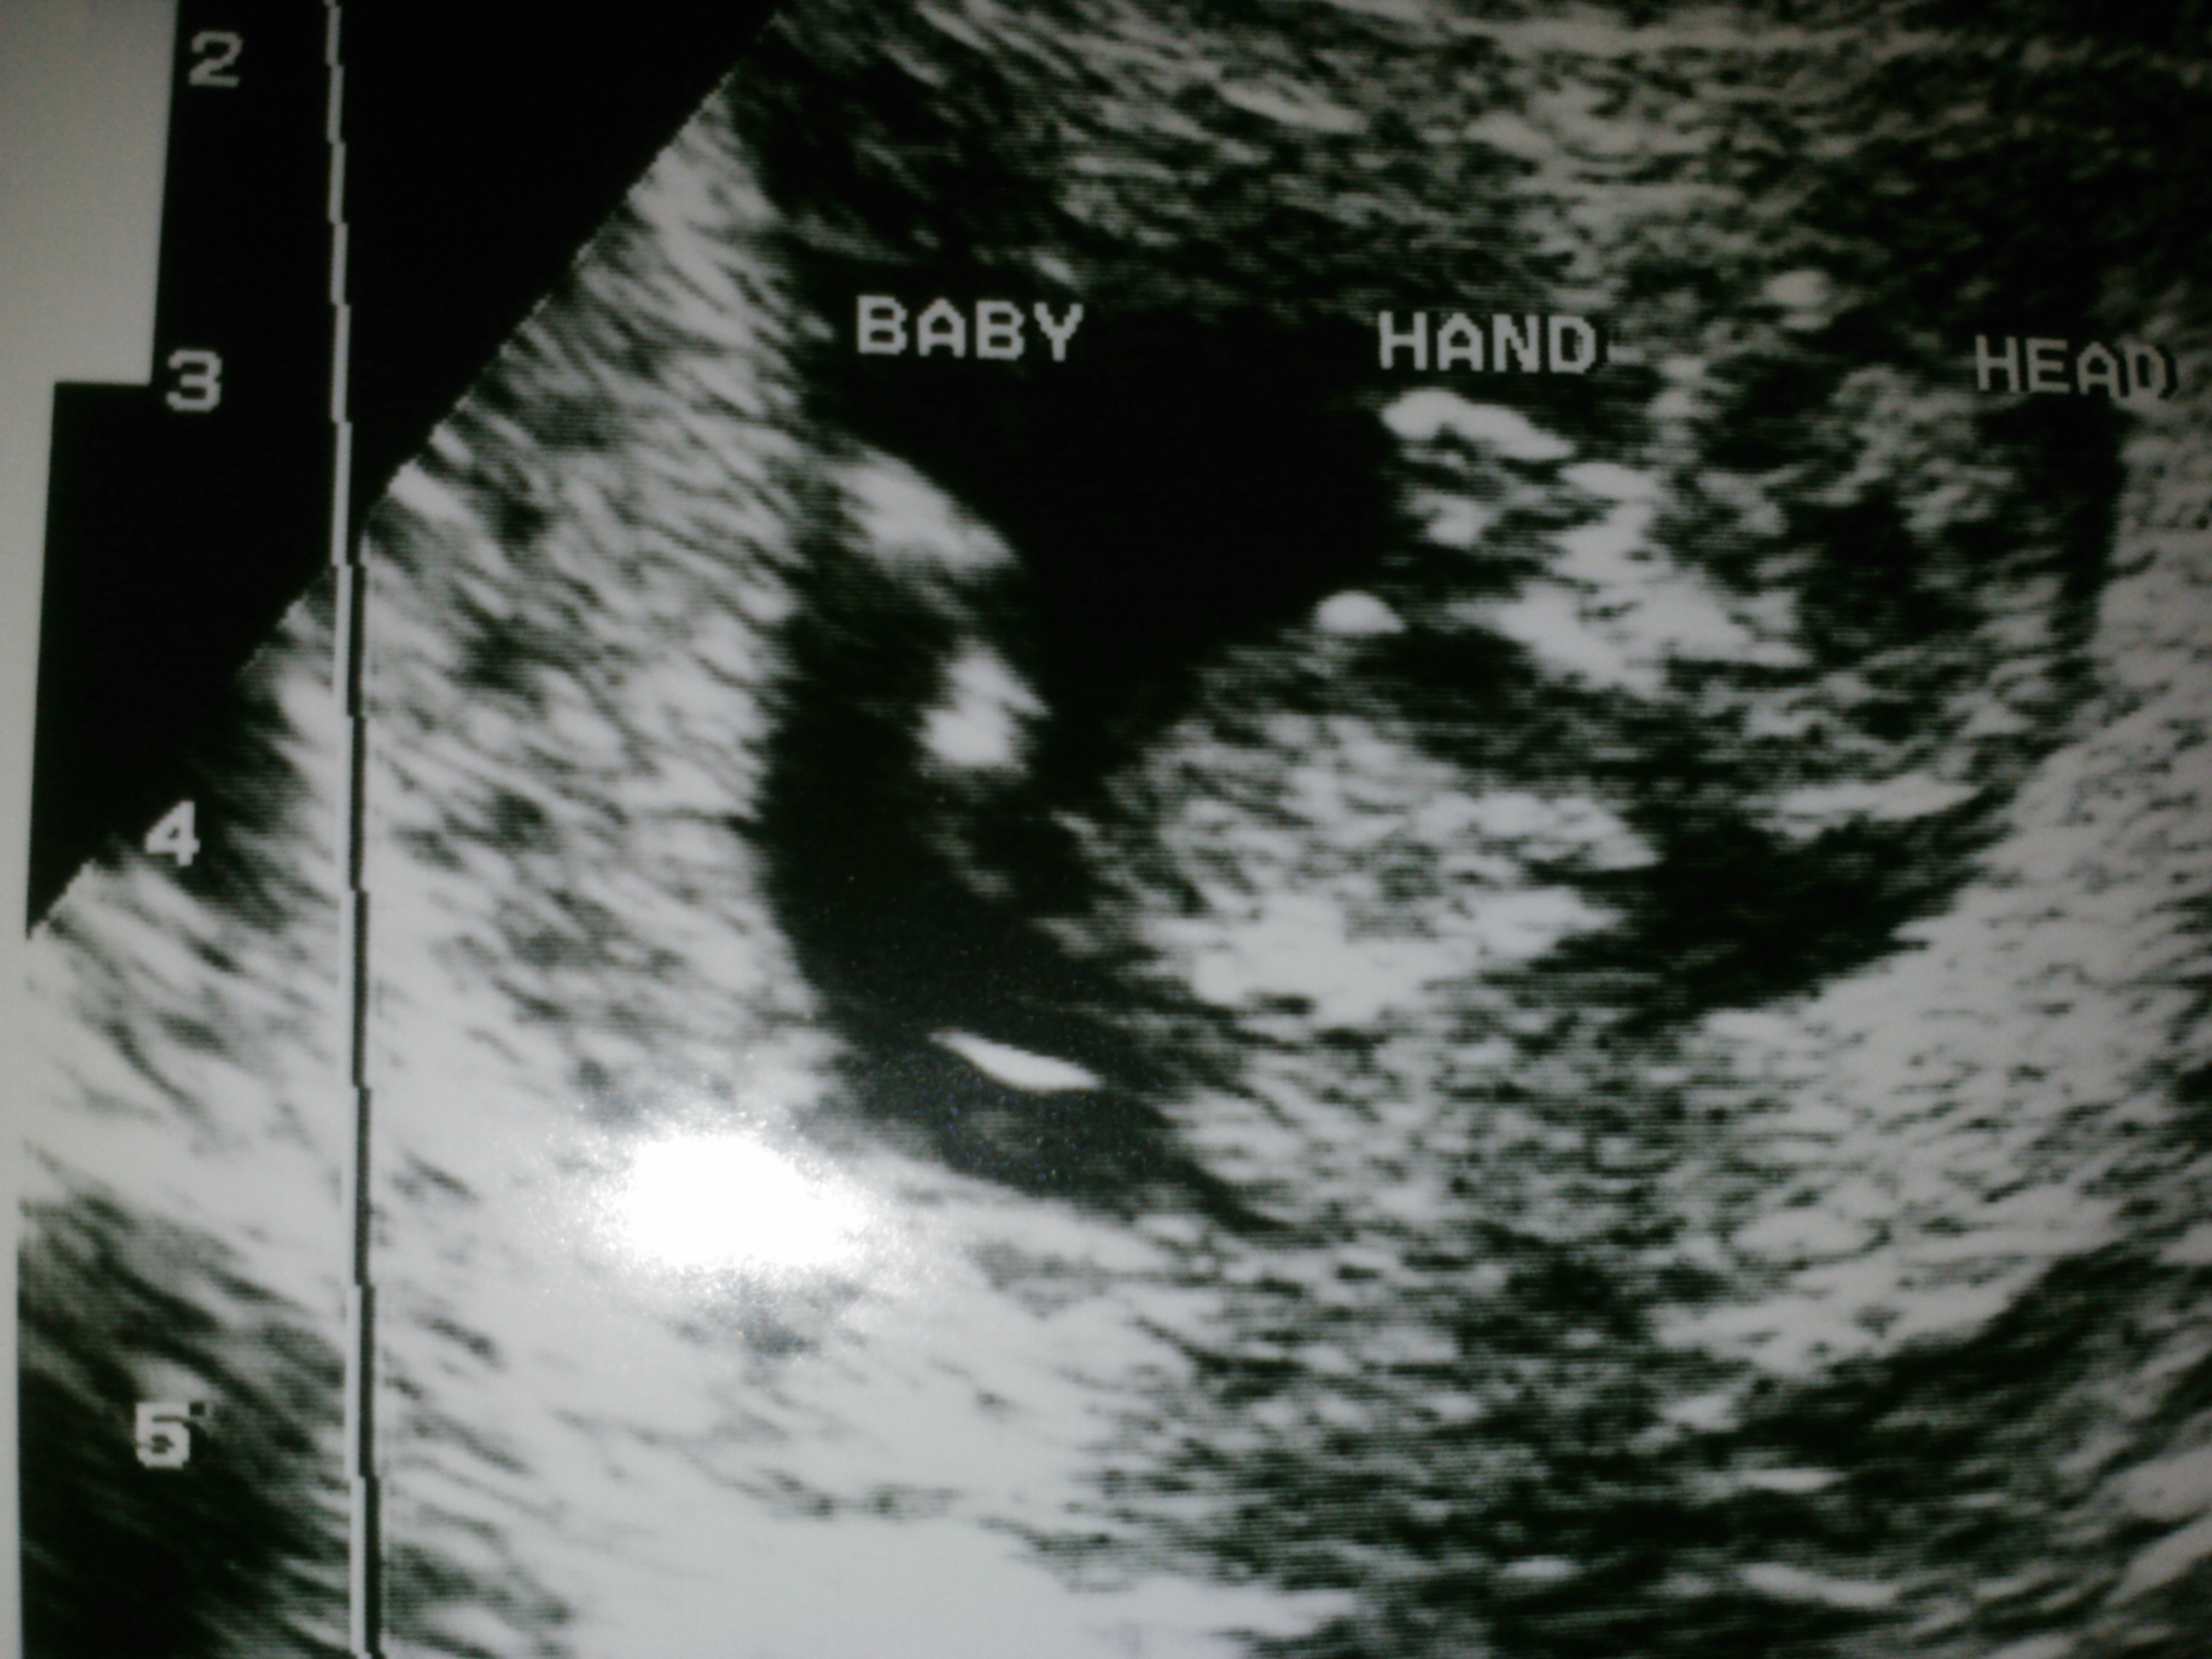

Attachment 5665 12 week ultrasound boy or girl???? Idle for sure if that is the nub or not but what do you think????

Idk if you can see the nub or not. What do you think?

Not sure as the pic isn't the best but I can see something sticking up that looks very boyish between the legs and belly area. Could be a nub, if so looks boyish to me.